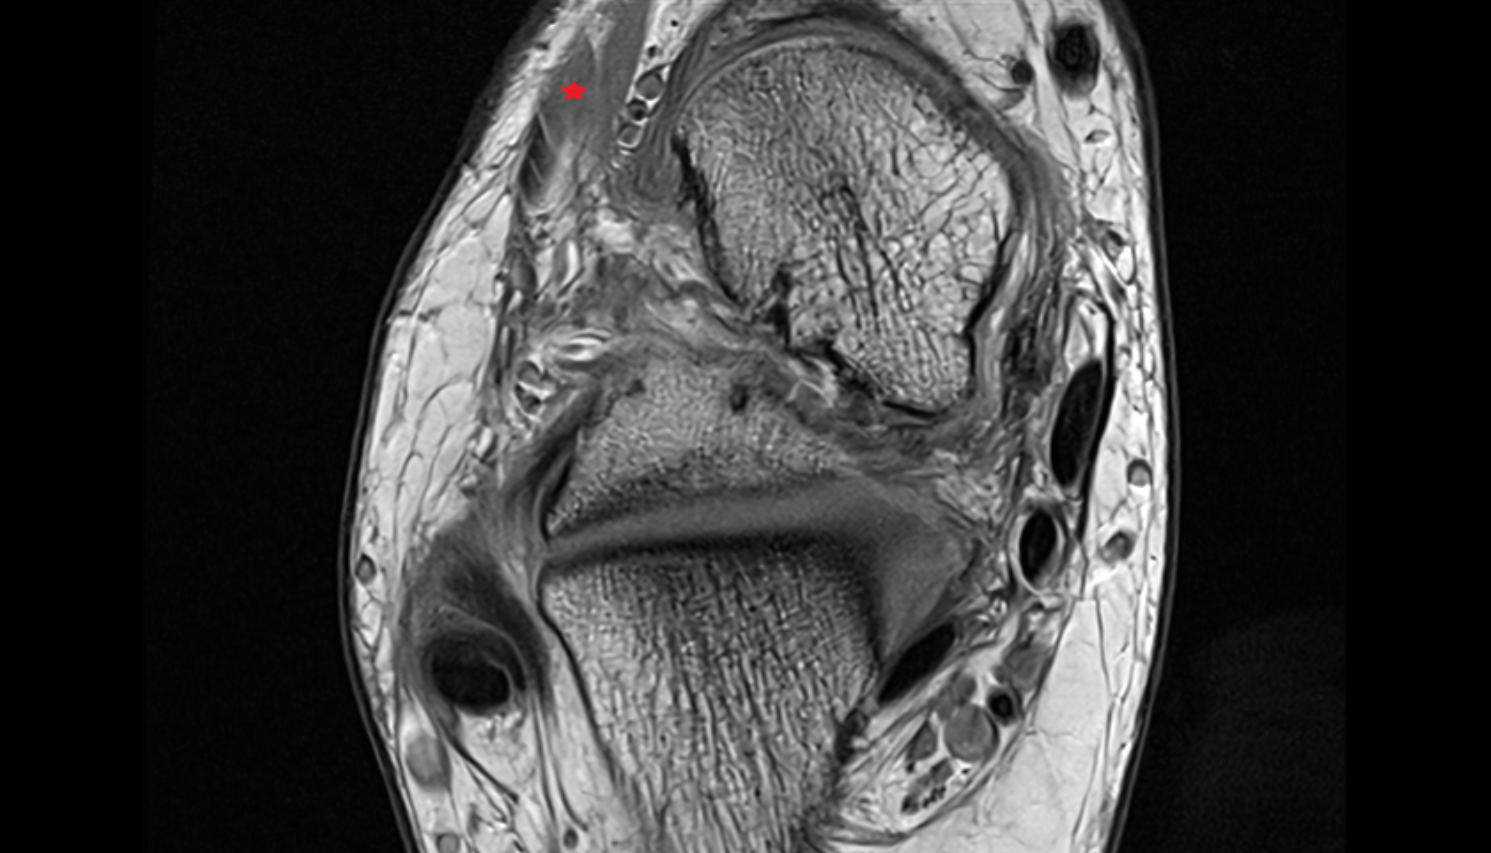

- Temporomandibular joint

- Mandibular condyle

- Mandibular fossa

- Articular disc of temporomandibular joint

- Deep part of masseter muscle

- Superficial part of masseter

- Temporalis muscle